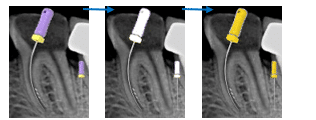

Step-by-Step Bypass Procedure

Step 1 — Improve access

Create straight-line access

Step 2 — Create space coronally

Use ultrasonic tips to create a 0.5–1 mm cuff around fragment.

Step 3 — Pre-bend small file

Use #10 K-file with sharp bend at the last 2–3 mm.

A straight file will not find the pathway.

Step 4 — Watch-winding motion

Use gentle watch-winding movement beside the fragment.

Never apply pushing pressure.

Step 5 — Enlarge pathway

Once #10 passes the fragment:

- #10 → #15 → #20

- Then rotary shaping

Step 6 — Confirm patency

When a #15 K-file reaches working length → patency restored.

Step 7 — Complete treatment

- Clean and shape normally

- Fragment remains inside canal.

- Considered part of obturation.